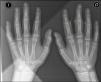

Varón de 14 años, sin antecedentes de interés, que consultó por cuadro de un año de evolución caracterizado por deformidad y tumefacción de patrón simétrico en la cara lateral de las articulaciones interfalángicas proximales (IFP) de los dedos segundo, tercero y cuarto, con predominio en la mano derecha (fig. 1A,B). No refería dolor, limitación, ni otras manifestaciones cutáneas o sistémicas asociadas.

La analítica, que incluyó hemograma, bioquímica, coagulación, velocidad de sedimentación globular, proteínaC reactiva, HLA-B27, factor reumatoide y anticuerpos antinucleares, resultó normal o negativa. La radiografía simple mostró un aumento de partes blandas en la segunda, tercera y cuarta articulaciones IFP en la mano derecha, sin datos de afectación articular u ósea asociados (fig. 2). En la resonancia magnética, se apreció edema y aumento de partes blandas del segundo, tercer y cuarto dedos de la mano derecha. No existían signos de sinovitis o colecciones asociadas (fig. 3). Se realizó una biopsia cutánea en la cual se objetivó hiperqueratosis compacta y engrosamiento de la dermis, con aumento del número de fibras colágenas y fibroblastos.